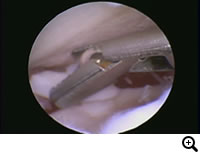

OCD / Osteochon dritisdissecans of the humeral head(離断性骨軟骨症)

症状:通常4〜8カ月齢で前肢を跛行します。初期は鎮痛剤に反応することもあります。診断がつかずに2〜3歳になり、遅れて再び跛行を呈する場合もあります。

OCD(離断性骨軟骨症)とは

上腕骨骨頭の関節軟骨が成長障害により厚みを増し、損傷を受けやすくなり、軟骨が浮きあがりはがれることで痛みを生じます。

診断

関節鏡検査

治療

関節鏡視下で軟骨フラップを切除します。大型犬の成長期の跛行は消炎鎮痛剤等による対症療法ですませず、跛行原因の早期診断、早期治療が重要です。